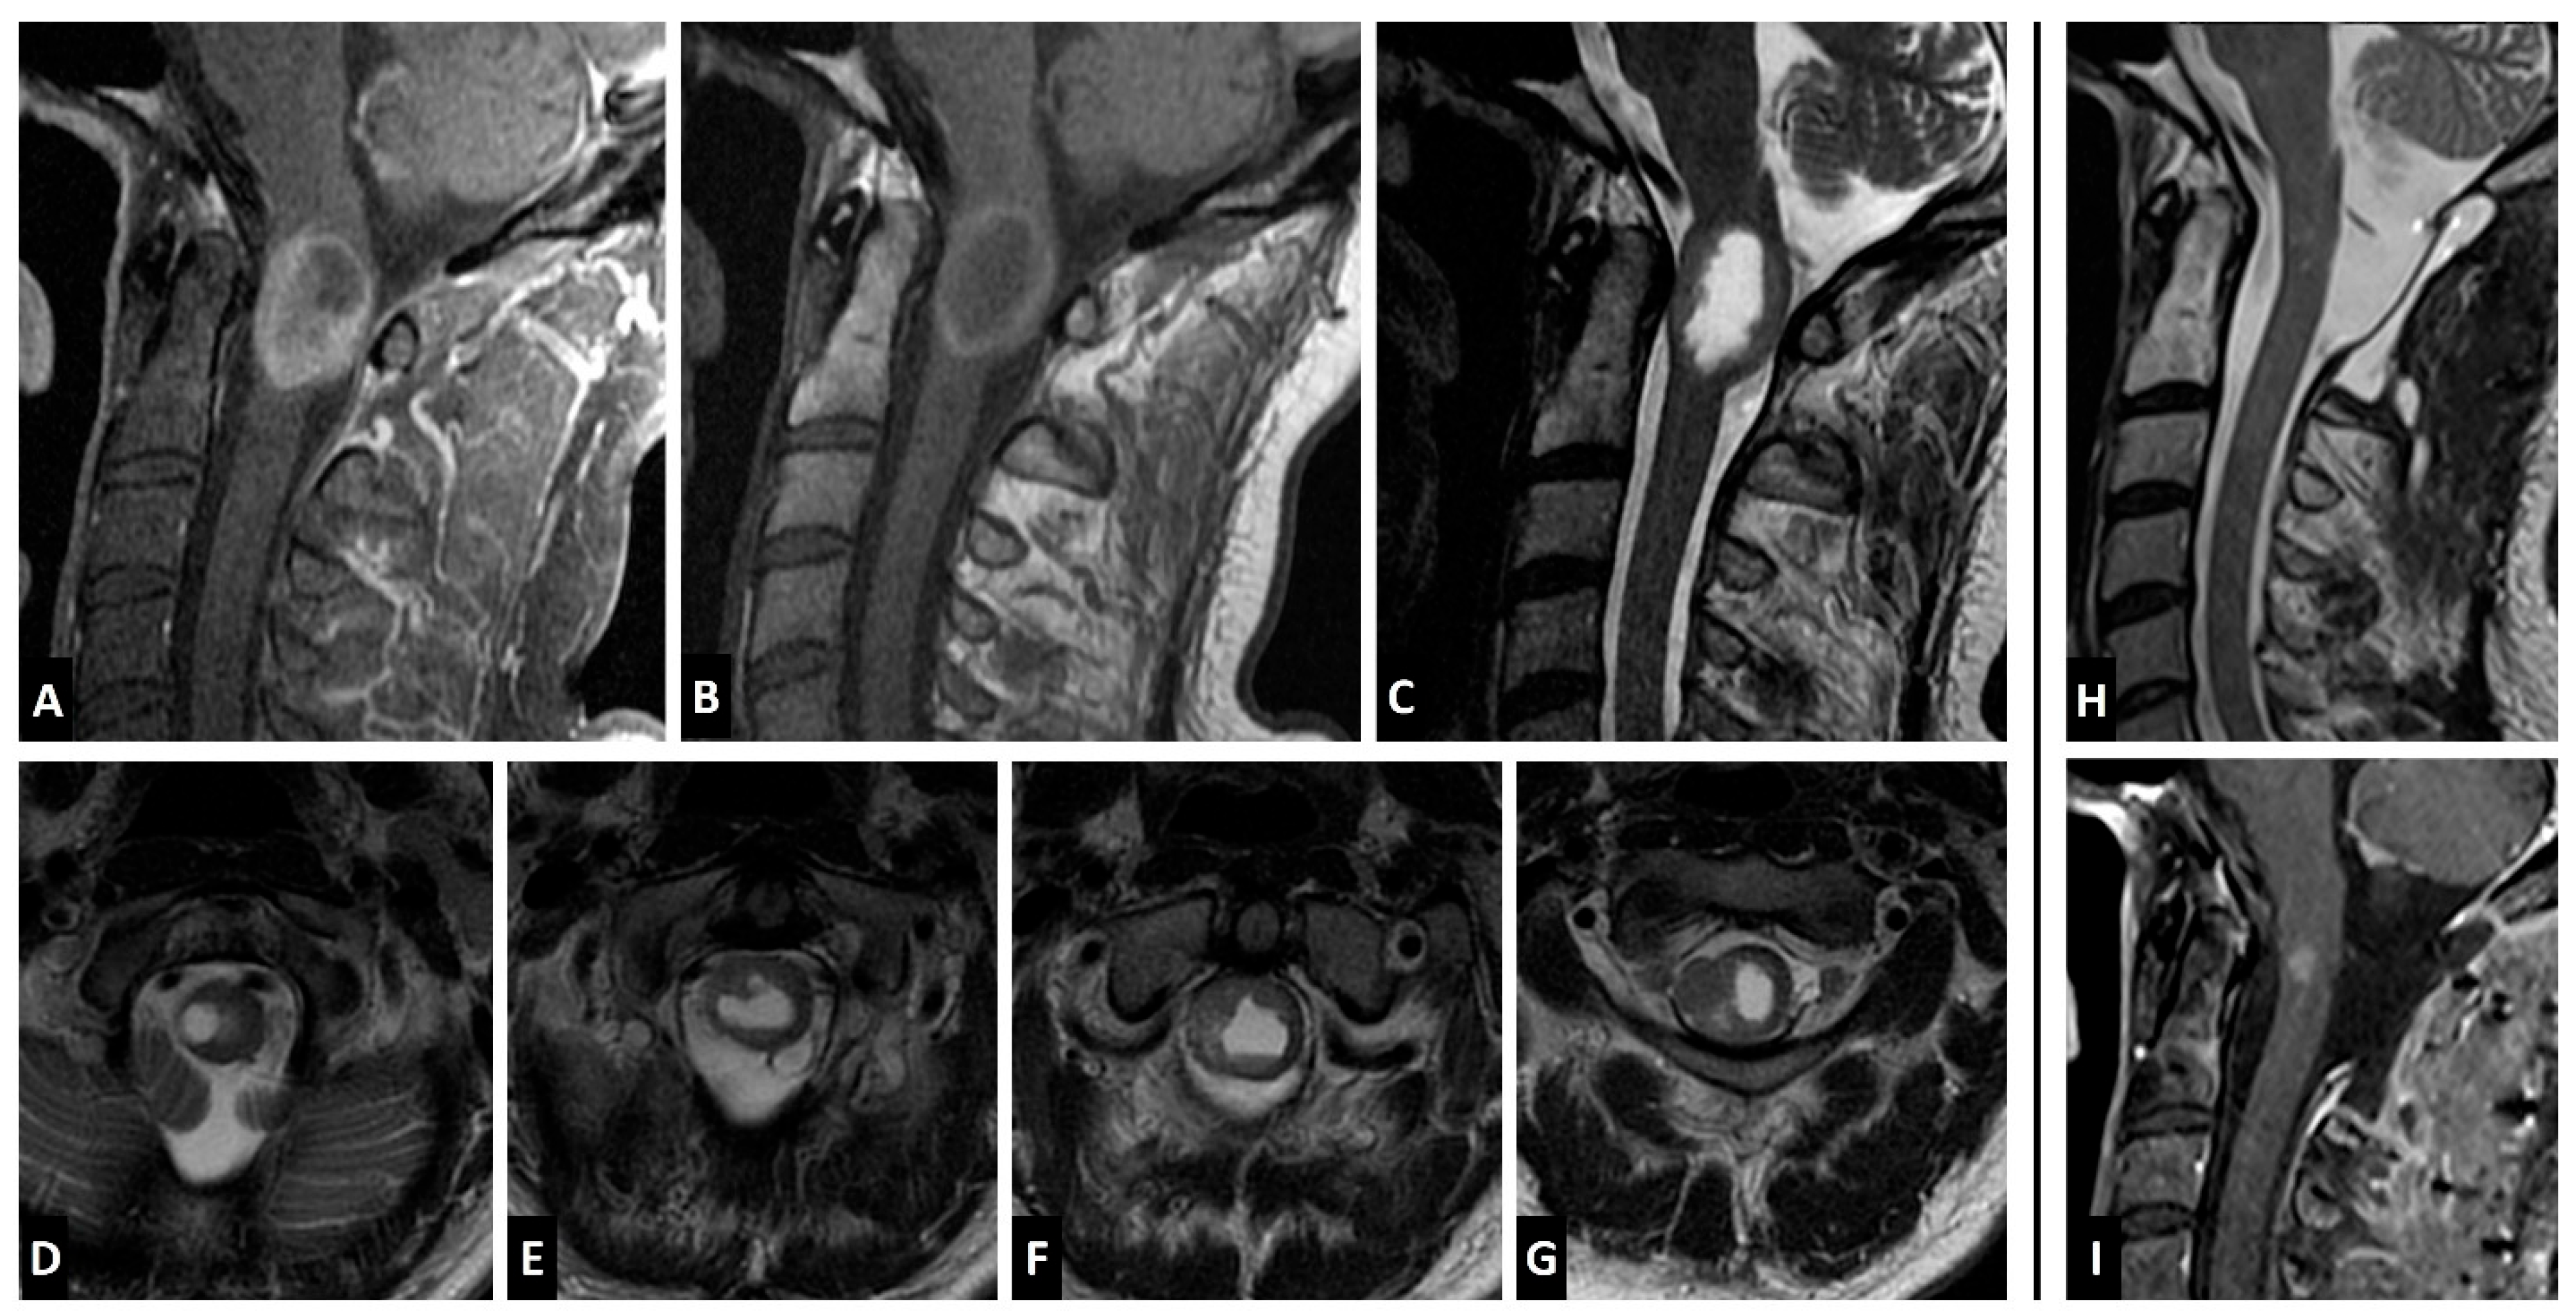

Case Report

4.3. Imaging Characteristics